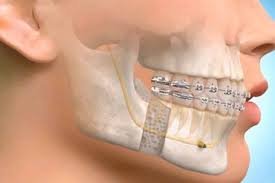

Oral & Maxillofacial Surgery

This surgical speciality diagnoses and treats defects, injuries, and diseases of the soft and hard tissues of the oral and maxillofacial (jaws and face) region.

• Procedures: Wisdom Tooth Extraction, Dental Cyst Removal, Jaw Fracture Management, Ranula Surgery.

• Benefit: Safe and expert surgical care for complex dental and facial issues.

Oral Surgery Procedure